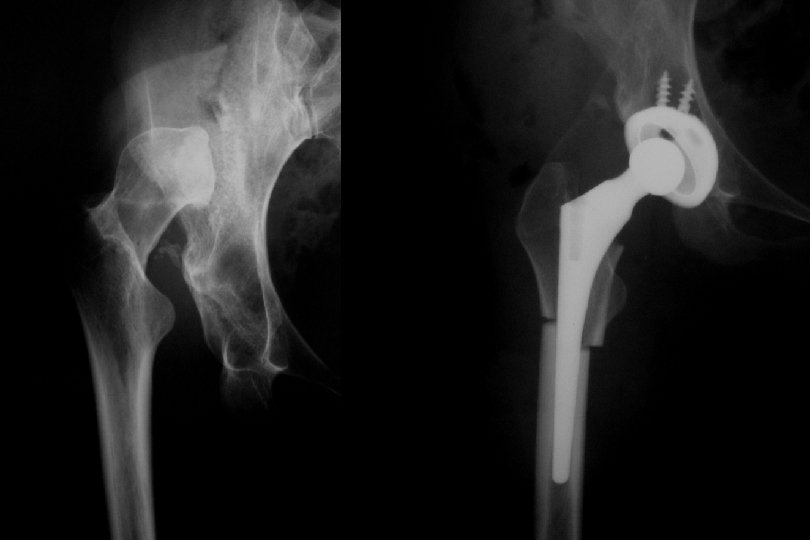

Genç adult Reluksasyon Hareket kısıtlılığı Avasküler nekroz Displazi, sublukse kalçalarda Ase-femur baş uyumunu artıran Girişimler Tamamen çıkıklara dokunulmamalı !!!

Sekonder dejeneratif osteoartrit TEMAS ALANI = 26. 7 cm Birim alana düşen yük miktarı = 23 kg/cm 2 TERS ORANTI

Adult • Artrodez !!! • Total Eklem Replasmanı • Genç ve aktif yaştalar • İyileştirilmiş malzemeler kullanılmalı • Hasta çok detaylı bilgilendirilmeli